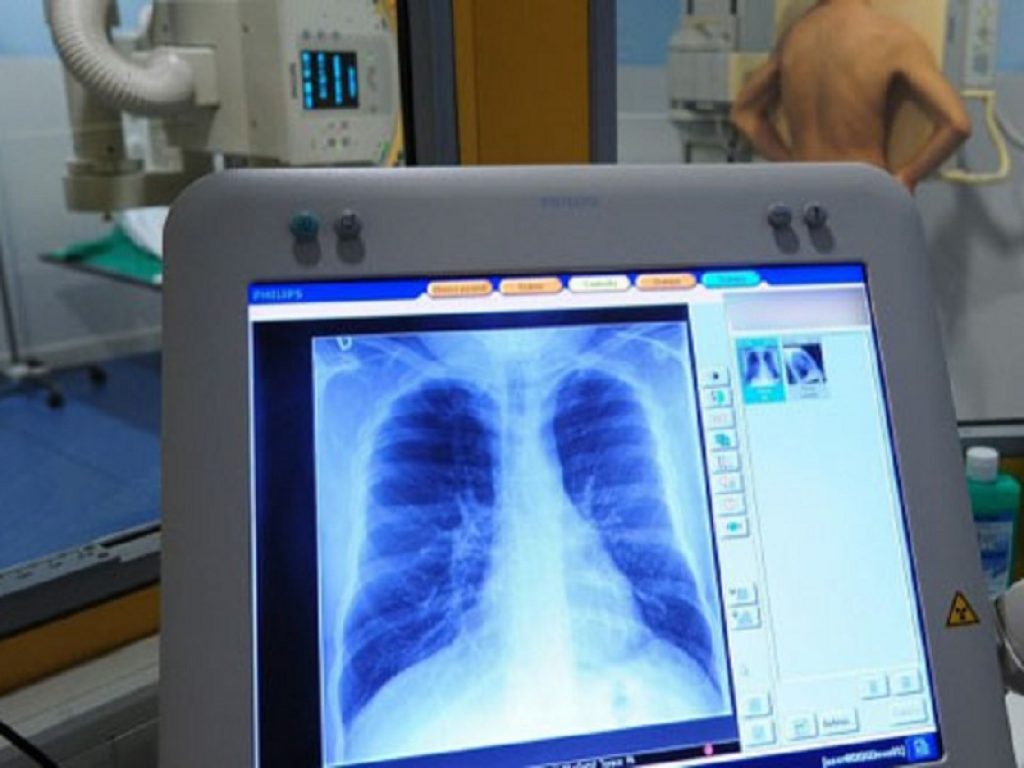

Come riportano gli autori nel background dello studio, l’infezione polmonare cronica da P. aeruginosa è una delle più importanti cause di mortalità e di morbilità nei pazienti con fibrosi cistica, ma se la terapia antibiotica viene iniziata prontamente, l’infezione può essere eradicata.